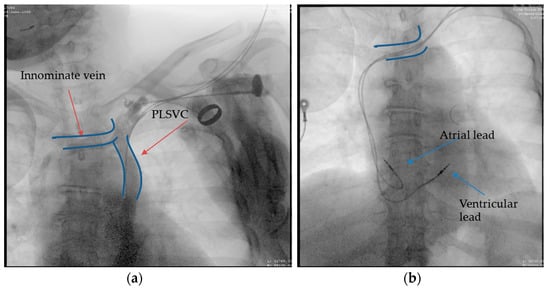

2.3. Case 3. (Type II)